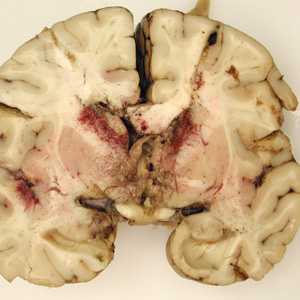

A seven-year-old, previously healthy child developed flu-like symptoms and rapidly progressive bulbar palsy, coma, and eventually death. Imaging revealed florid ventriculitis. A viral etiology was initially suspected. The autopsy revealed extensive necrotizing (mixed inflammatory, occasional giant cells, vasculitic) granulomatous encephalitis (Figures A and B), with a subependymal necroinflammatory process. Tissue sections of the brain were made and stained with hematoxylin and eosin (H&E). Images of the brain and subsequent tissue sections (Figures C and D, taken at 1000x oil magnification) were sent to DPDx for diagnostic assistance. What is your diagnosis? Based on what criteria? What further testing is recommended?

This was a case of granulomatous amebic encephalitis (GAE) caused by Balamuthia mandrillaris. Diagnostic features were:

- the pathology of the infection, manifesting as rapid granulomatous encephalitis.

- the presence of thick-walled cysts (Figures C and D), containing a fibrous outer wall (ectocyst) and an inner wall (endocyst) with granular cytoplasm and prominent globules.

Balamuthia is one of four genera of typically free-living amoebae implicated in amebic encephalitis, the other three being Naegleria, Acanthamoeba, and only recently, Sappinia. Amoebae enter the body through nasal passages or broken skin and can invade the central nervous system by hematogenous dissemination. Identification to the genus level is sometimes difficult based on morphology of the amoebae alone. In this particular case, Naegleria could have been ruled-out by the presence of cysts, as this genus does not produce cysts in human tissue. This case was confirmed by an immunofluorescence test and real-time PCR using Balamuthia-specific primers. Cultivation of the causal organism may also prove useful.